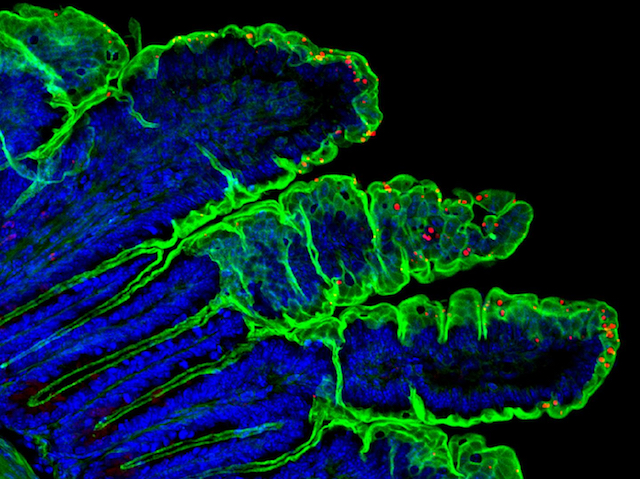

Parlant de Capes+

Parlant de Capes+24 d'agost de 2018